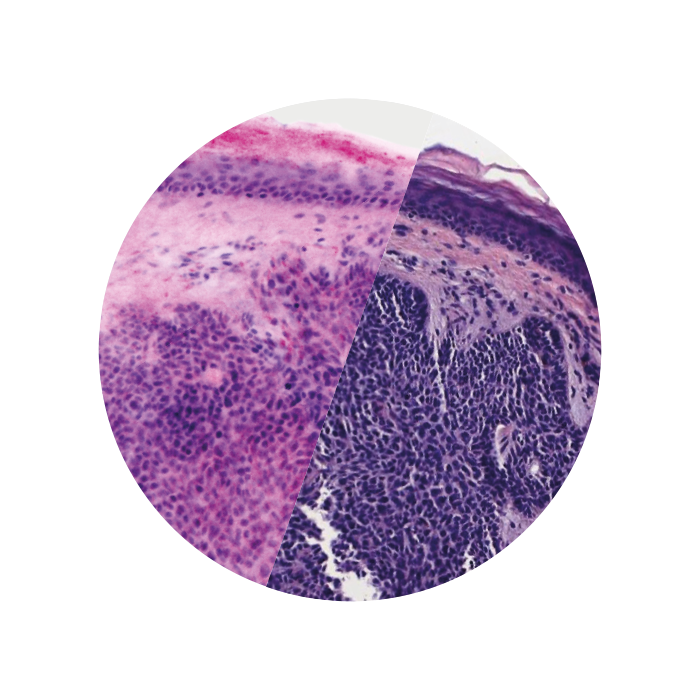

Images courtesy of Dr Javiera Pérez-Anker.

Basal cell carcinoma; imaged with the VivaScope 2500 (left) and after H&E staining (right)

Image courtesy of Dr. Anna Crescenzi, Department of University Hospital Campus Bio-Medico, Rome.